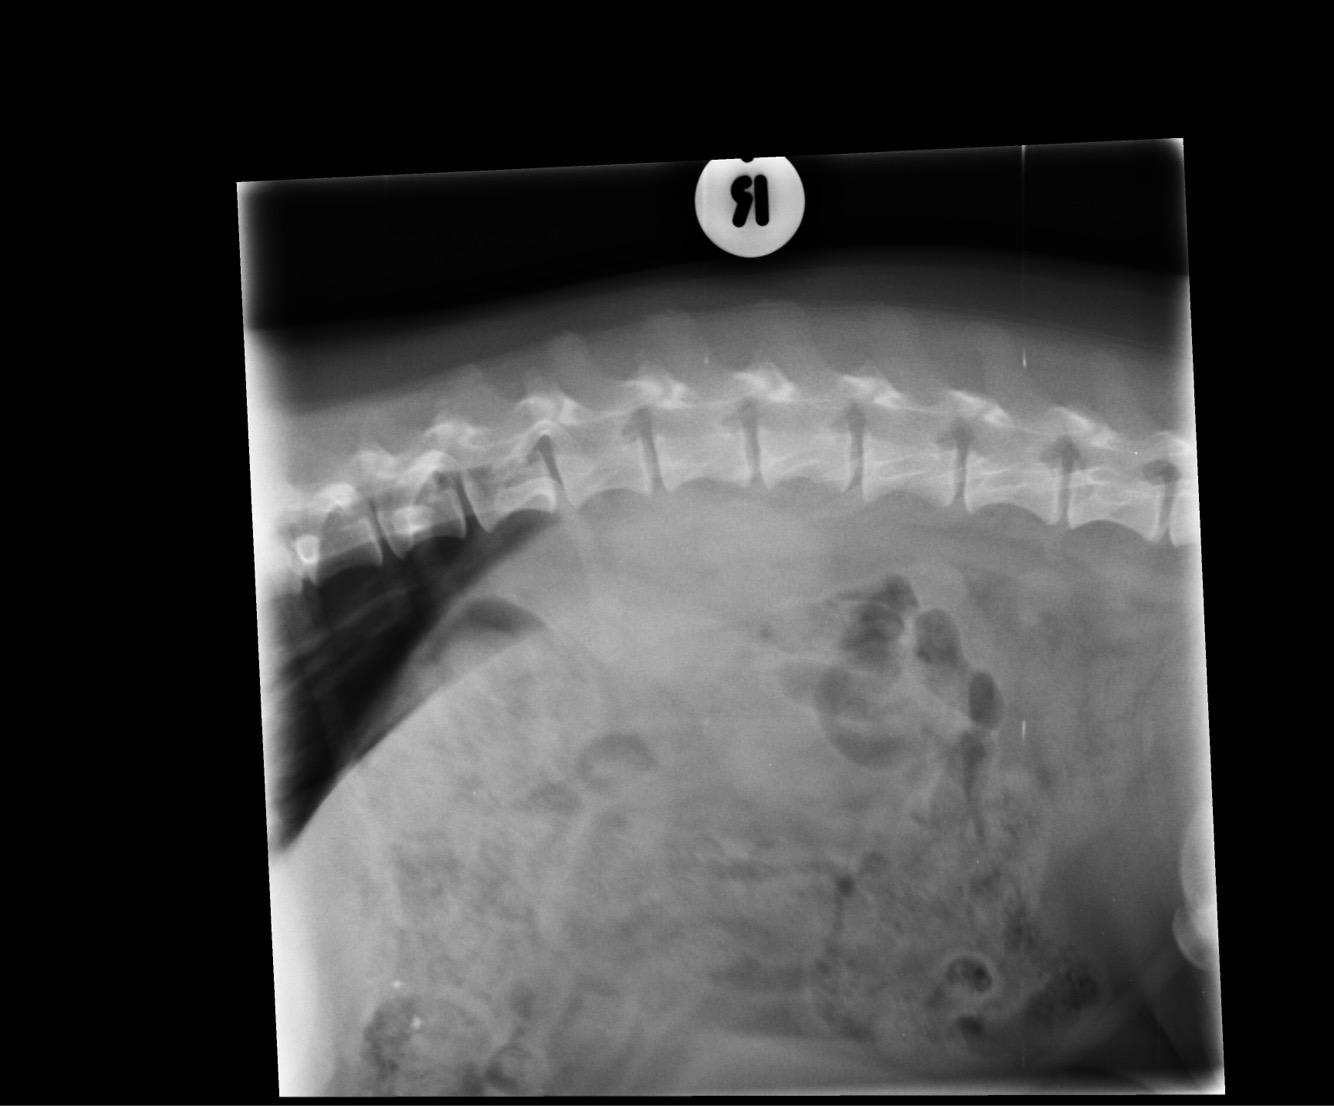

Are my dog's X-rays enough to diagnose a spleen hemangiosarcoma?

Pet's info: Dog | Dachshund | Male | neutered | 6 years and 6 months old | 20 lbs

Could you please advise as to whether this is adequate imagining to determine a sarcoma? Could it possibly be a hemangiosarcoma?

There is possibly a mass on the left side attached to the spleen, but these x-rays are not sufficient to tell. If there is a mass on the spleen, the most likely possibilities are hematoma (basically a bruise), hemangioma (a benign tumor) and a hemangiosarcoma. So yes, if there is a mass there is could be a hemangiosarcoma, however ultrasound would be needed to get a better view, and ultimately the mass (likely the entire spleen) would need to be removed and biopsided to get a specific diagnosis.